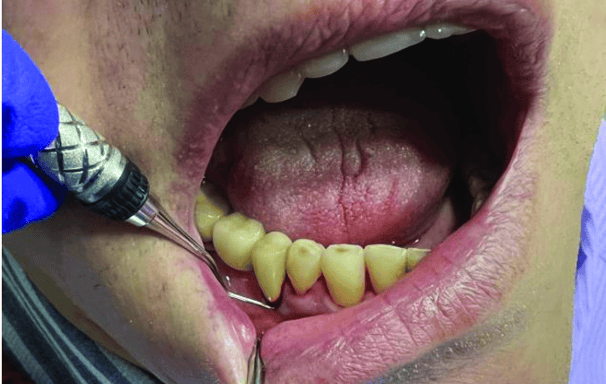

Destartraje supragingival

Consiste en eliminar el sarro y la placa que se acumulan sobre la línea de las encías. Se realiza con instrumentos manuales o ultrasonido para prevenir enfermedades periodontales.

Destartraje subgingival

Se enfoca en la limpieza de debajo de la línea de las encías para eliminar el sarro y la placa que no se puede ver a simple vista. Esto ayuda a reducir la inflamación y la infección de las encías.